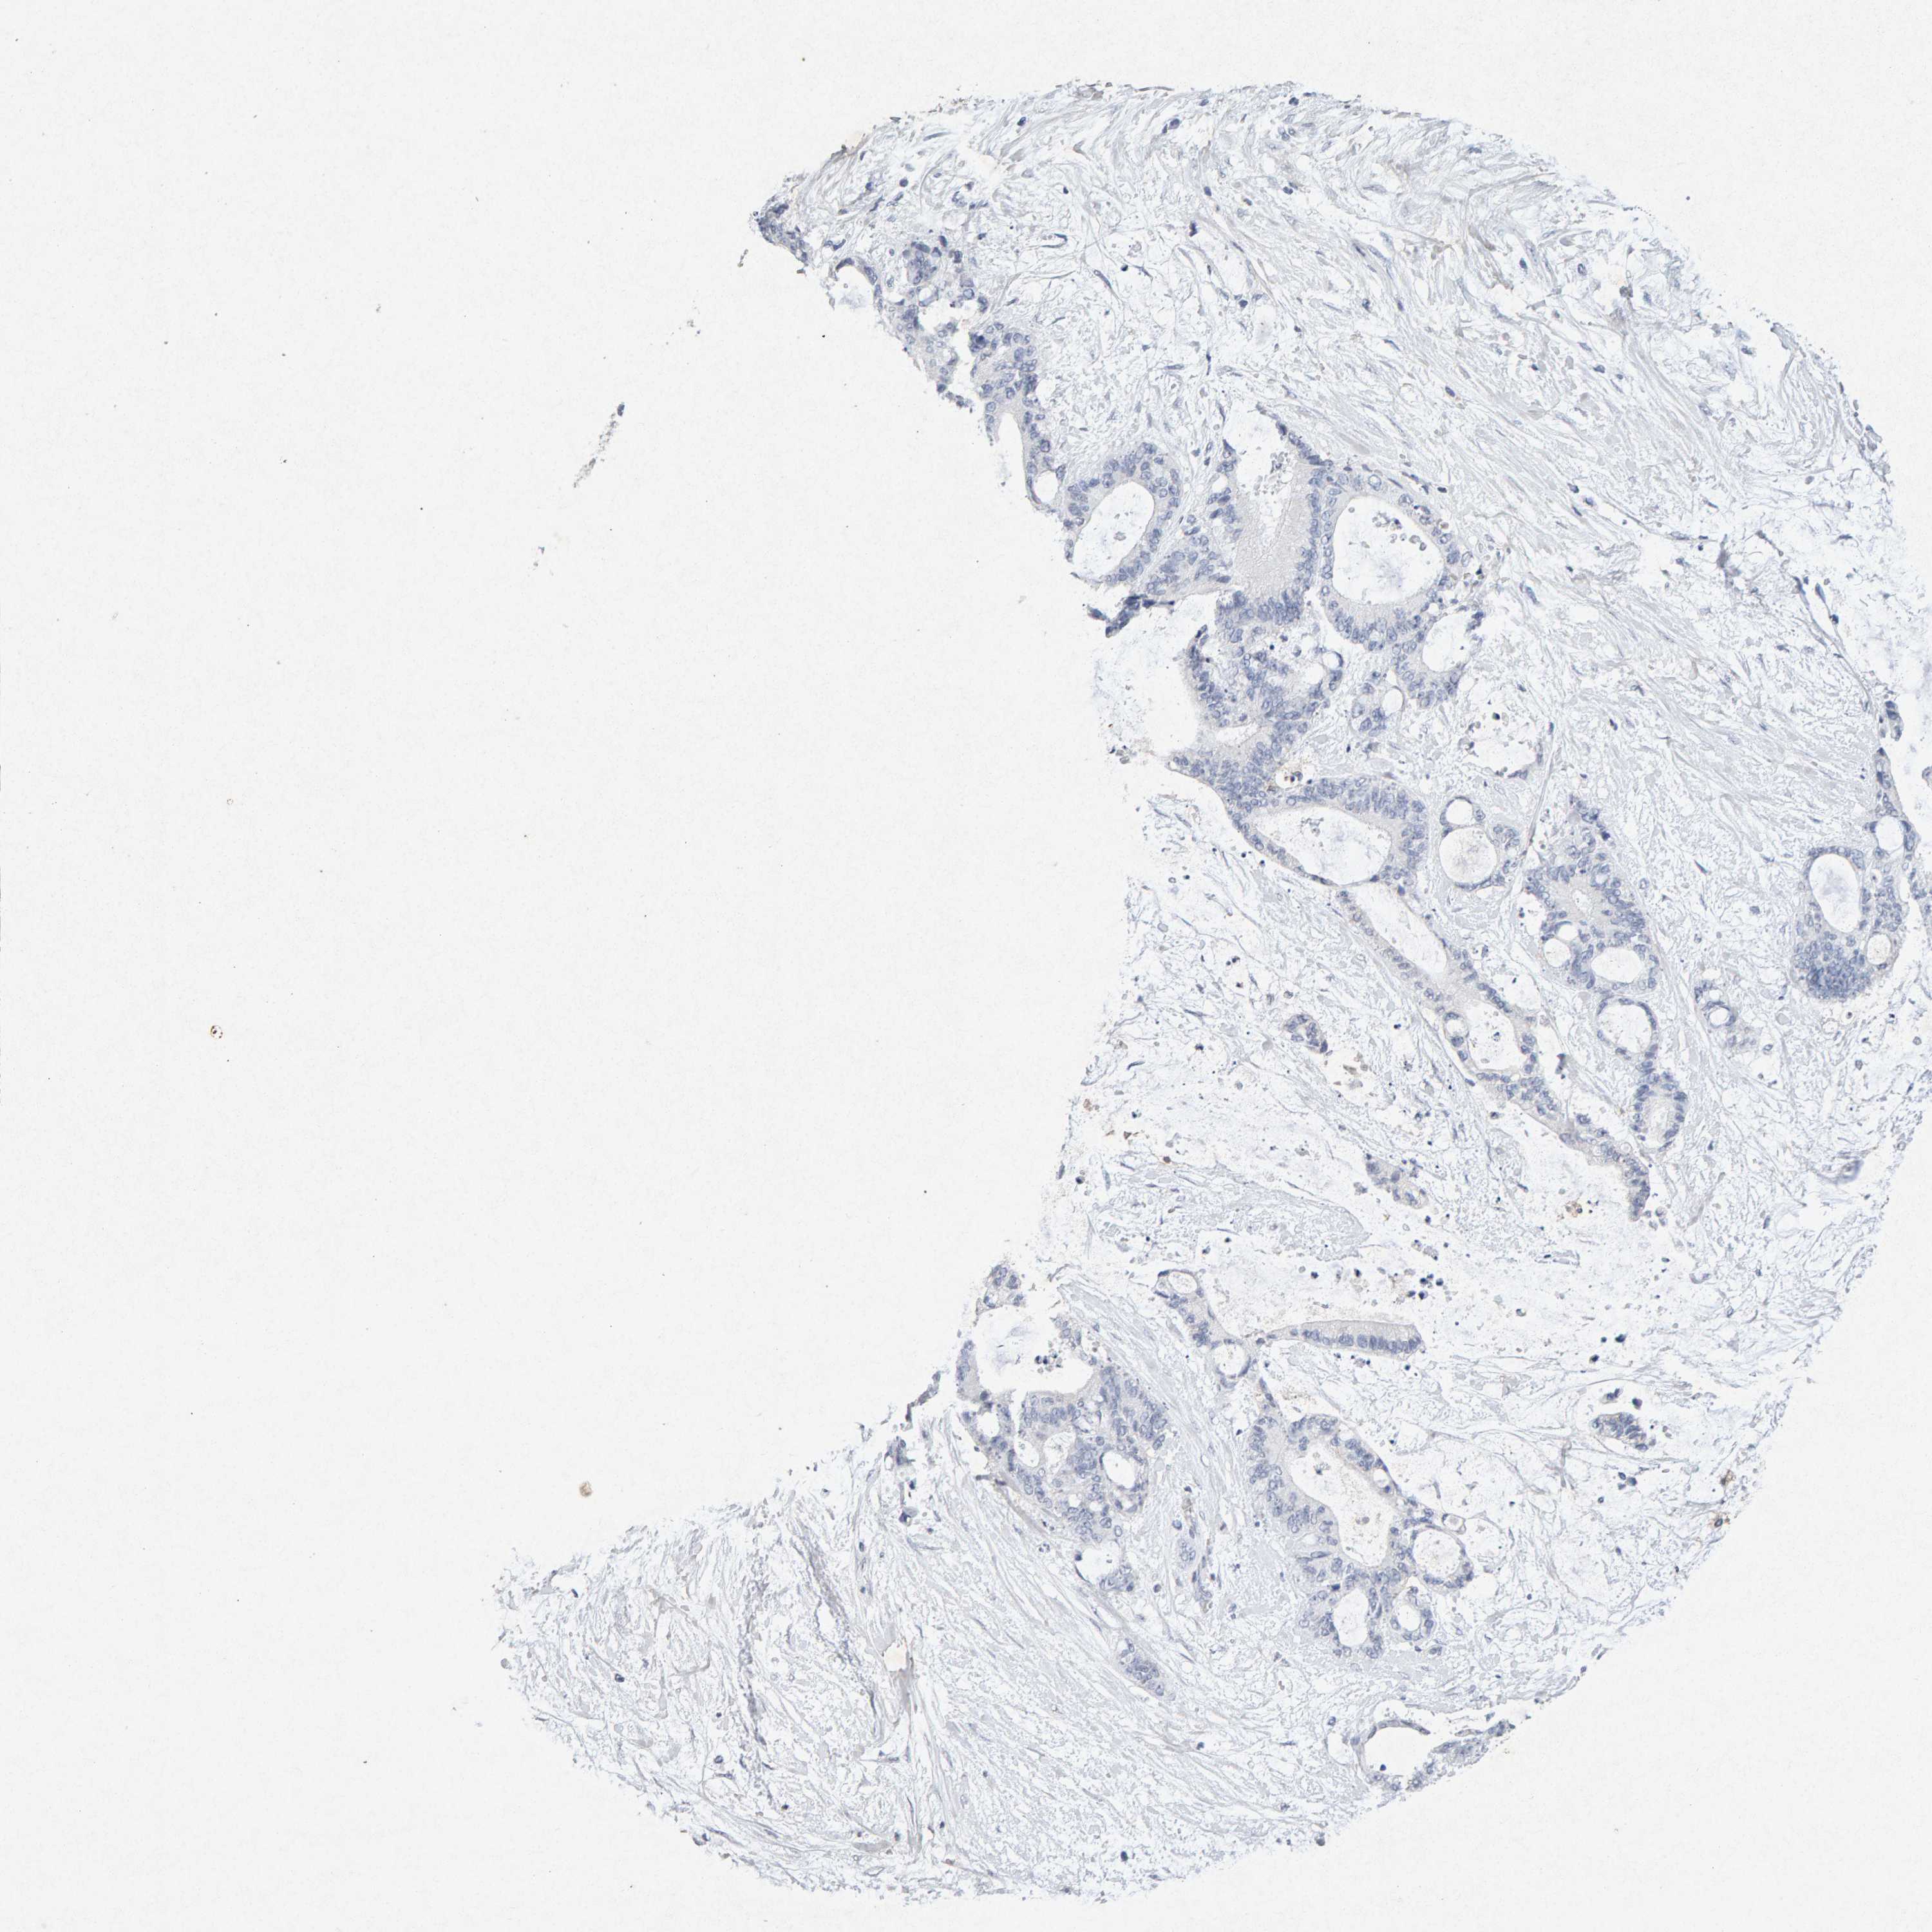

LIVER CANCER - Protein expressioni

A mouse-over function shows sample information and annotation data. Click on an image to view it in a full screen mode. Samples can be filtered based on level of antibody staining by selecting one or several of the following categories: high, medium, low and not detected. The assay and annotation is described here.

Note that samples used for immunohistochemistry by the Human Protein Atlas do not correspond to samples in the TCGA dataset.

Antibody stainingi

Antibody staining in the annotated cell types in the current human tissue is reported as not detected, low, medium, or high, based on conventional immunohistochemistry profiling in selected tissues. This score is based on the combination of the staining intensity and fraction of stained cells.

Each image is clickable and will lead to virtual microscopy that enables deeper exploration of all samples and also displays staining intensity scores, fraction scores and subcellular localization as well as patient and tissue information for each sample.

Antibody CAB022442

Antibody CAB022443

Staining

High

Medium

Low

Not detected

Intensity

Strong

Moderate

Weak

Negative

Quantity

>75%

75%-25%

<25%

None

Location

Nuclear

Cytoplasmic/membranous

Cytoplasmic/membranous,nuclear

Cholangiocarcinoma

Carcinoma, Hepatocellular, NOS